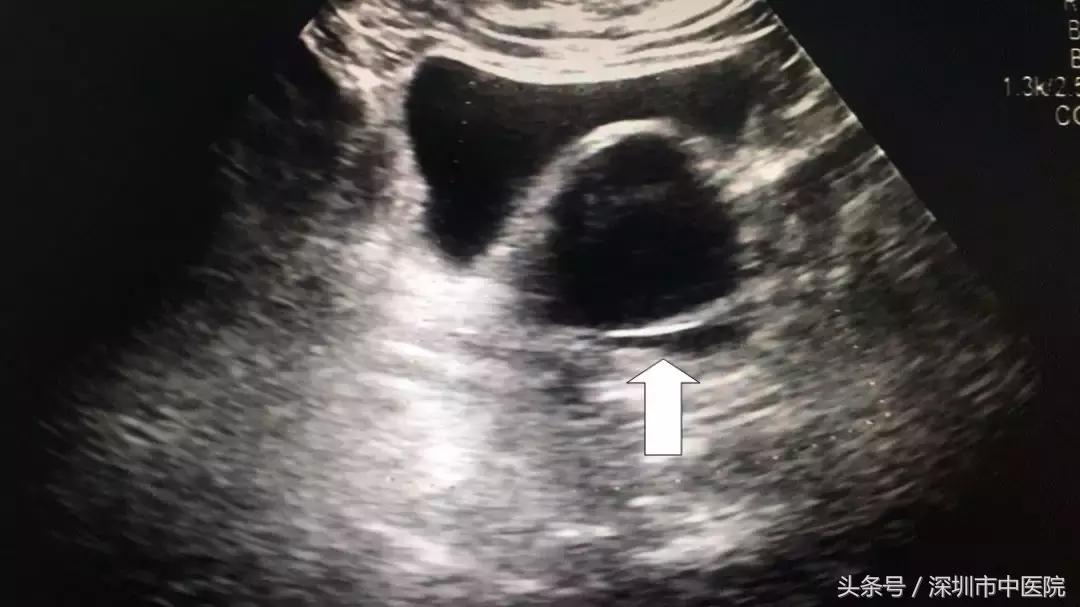

到深圳市中医院B超检查发现,右侧附件有肿瘤,而且它居然有7公分这么大!

16:08手术正式开始,杜主任先用阴道拉钩打开林阿姨的阴道,暴露后穹隆,从后穹隆切开2cm大的小孔,进入腹腔,置入“自制手套式”Trocar,镜下可以看见肿瘤在右侧卵巢,大小约7cm×7cm×6cm,和周围的组织肠管、侧盆壁居然都有不同程度的粘连。